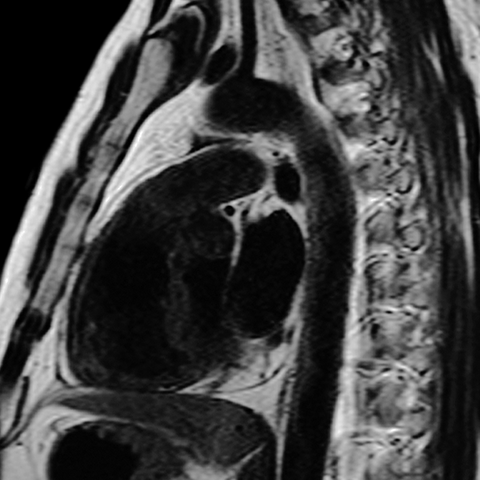

Normal Pericardium (Sagittal MR) [5 of 8]